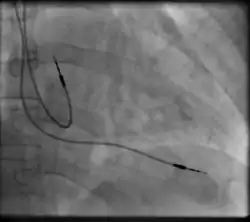

Transvenous pacing, when used for temporary pacing, is an alternative to transcutaneous pacing. A pacemaker wire is placed into a vein, under sterile conditions, and then passed into either the right atrium or right ventricle. The pacing wire is then connected to an external pacemaker outside the body. Transvenous pacing is often used as a bridge to permanent pacemaker placement. It can be kept in place until a permanent pacemaker is implanted or until there is no longer a need for a pacemaker and then it is removed.

Permanent pacing with an implantable pacemaker involves transvenous placement of one or more pacing electrodes within a chamber, or chambers, of the heart, while the pacemaker is implanted under the skin below the clavicle. The procedure is performed by incision of a suitable vein into which the electrode lead is inserted and passed along the vein, through the valve of the heart, until positioned in the chamber. The procedure is facilitated by fluoroscopy which enables the physician to view the passage of the electrode lead. After satisfactory lodgement of the electrode is confirmed, the opposite end of the electrode lead is connected to the pacemaker generator.